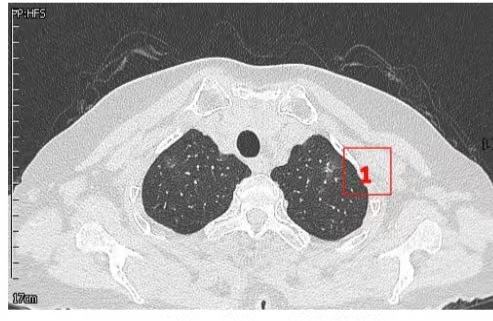

患者女性,71岁,因“发现左肺多发结节2周”入院。胸部CT提示左肺多发磨玻璃结节,较大者位于左肺上叶,呈类圆形,边界清晰,最大直径约9mm。该CT表现高度提示恶性可能。鉴于患者结节数量较多,为减少术中肺组织损伤,术前于CT引导下行经皮肺结节定位术,继而实施胸腔镜下左肺楔形切除术。术中共切除肺部结节6枚。术后病理示:左肺上叶较大结节(4号)为微浸润腺癌,其余5枚结节均为原位癌。患者术后恢复良好,于术后第1天拔除胸腔引流管,第4天顺利出院。

▲术前定位